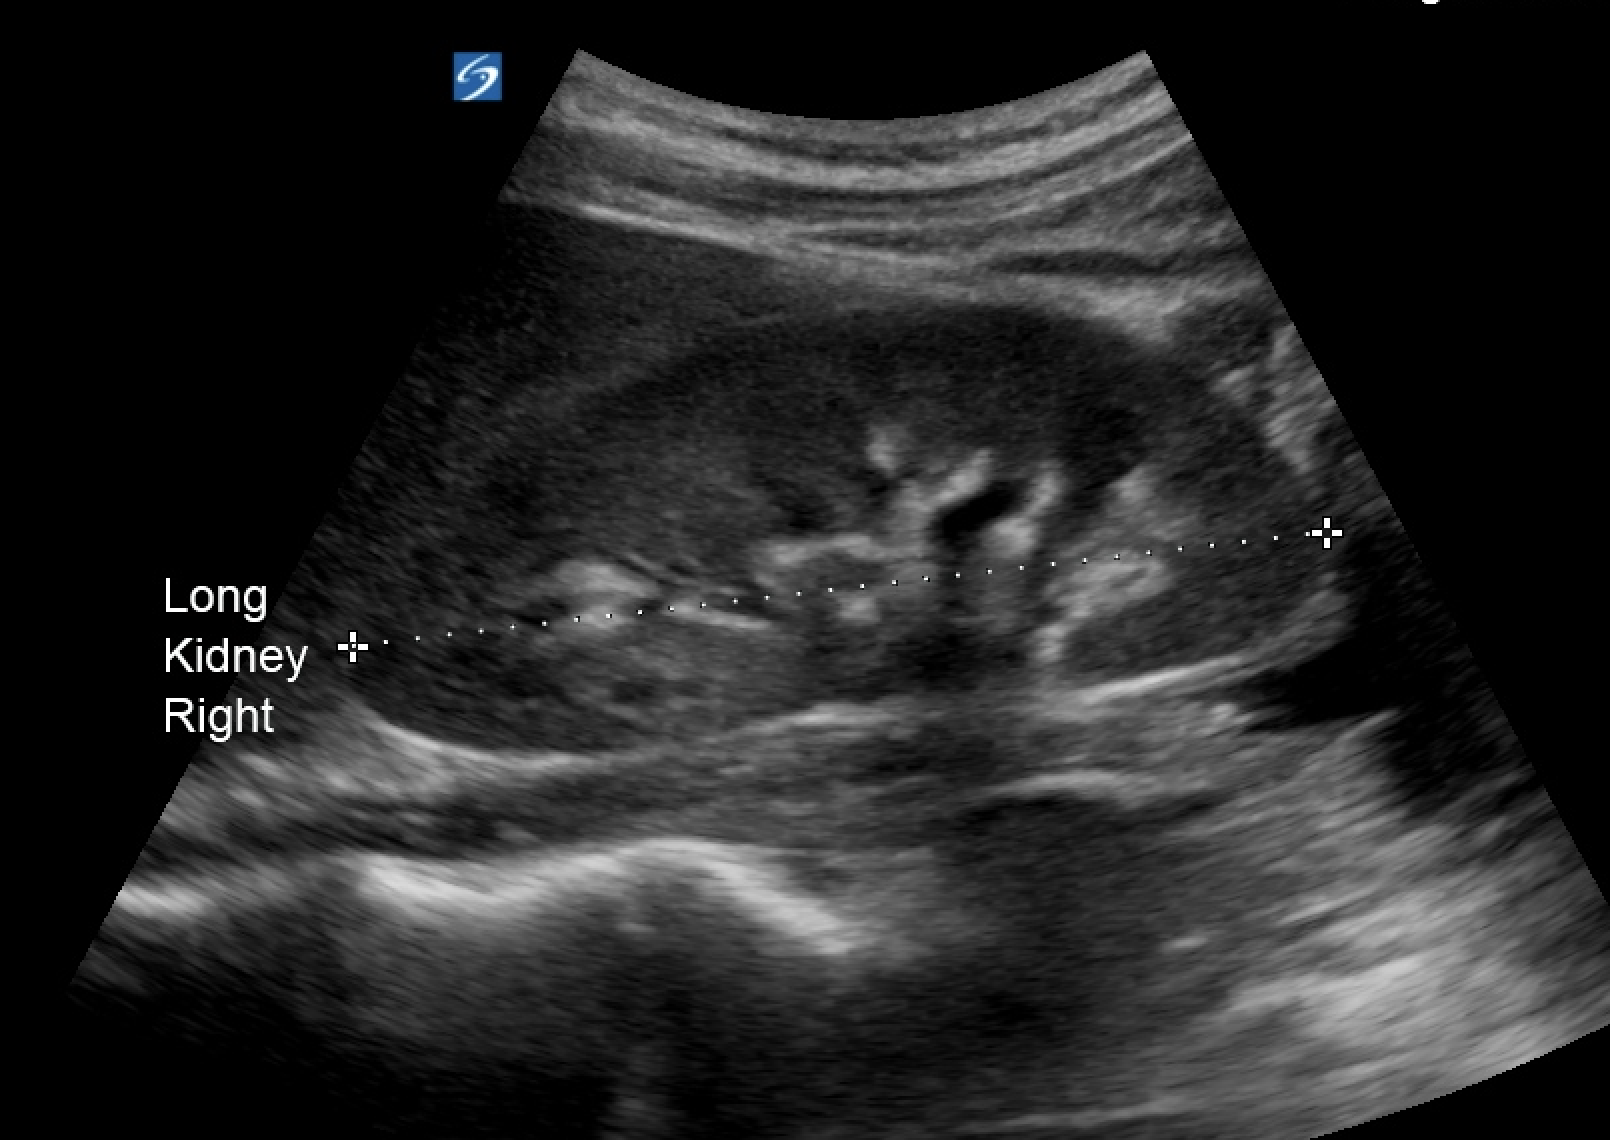

When looking at the kidney, each kidney should be 9-12cm long with a regular contour. The parenchyma typically is hypoechoic similar to normal liver. The bright white of gerota's fascia should be easily imaged.

Normal renal architecture and length

Gerota's fascia: hyperechoic line around the kidney